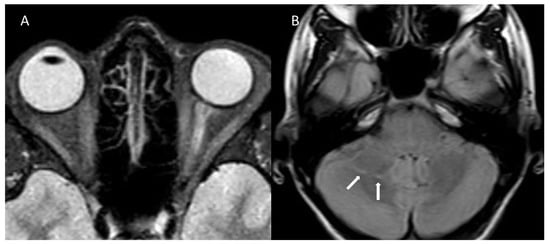

| MRI | Left optic nerve: hyperintensity (T2) Two millimetric T2 hyperintense cerebellar foci | Right optic nerve: hyperintensity (STIR), contrast enhancement ADEM outcomes | Right optic nerve: small hyperintensity (T2) Multiple juxtacortical, infratentorial, and periventricular demyelinating lesions; four lesions with contrast enhancement | Right and left optic nerves: retrobulbar bilateral swelling, contrast enhancement |